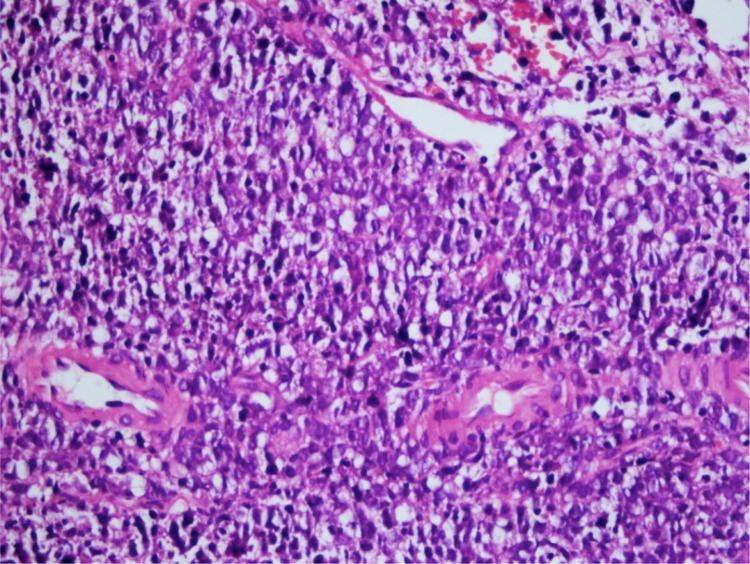

Hoarseness: an unusual presentation of primary thyroid lymphoma with laryngeal infiltration.

Braz J Otorhinolaryngol. 2016 Nov-Dec;82(6):737-740. doi: 10.1016/j.bjorl.2015.05.006. Epub 2015 Sep 7.